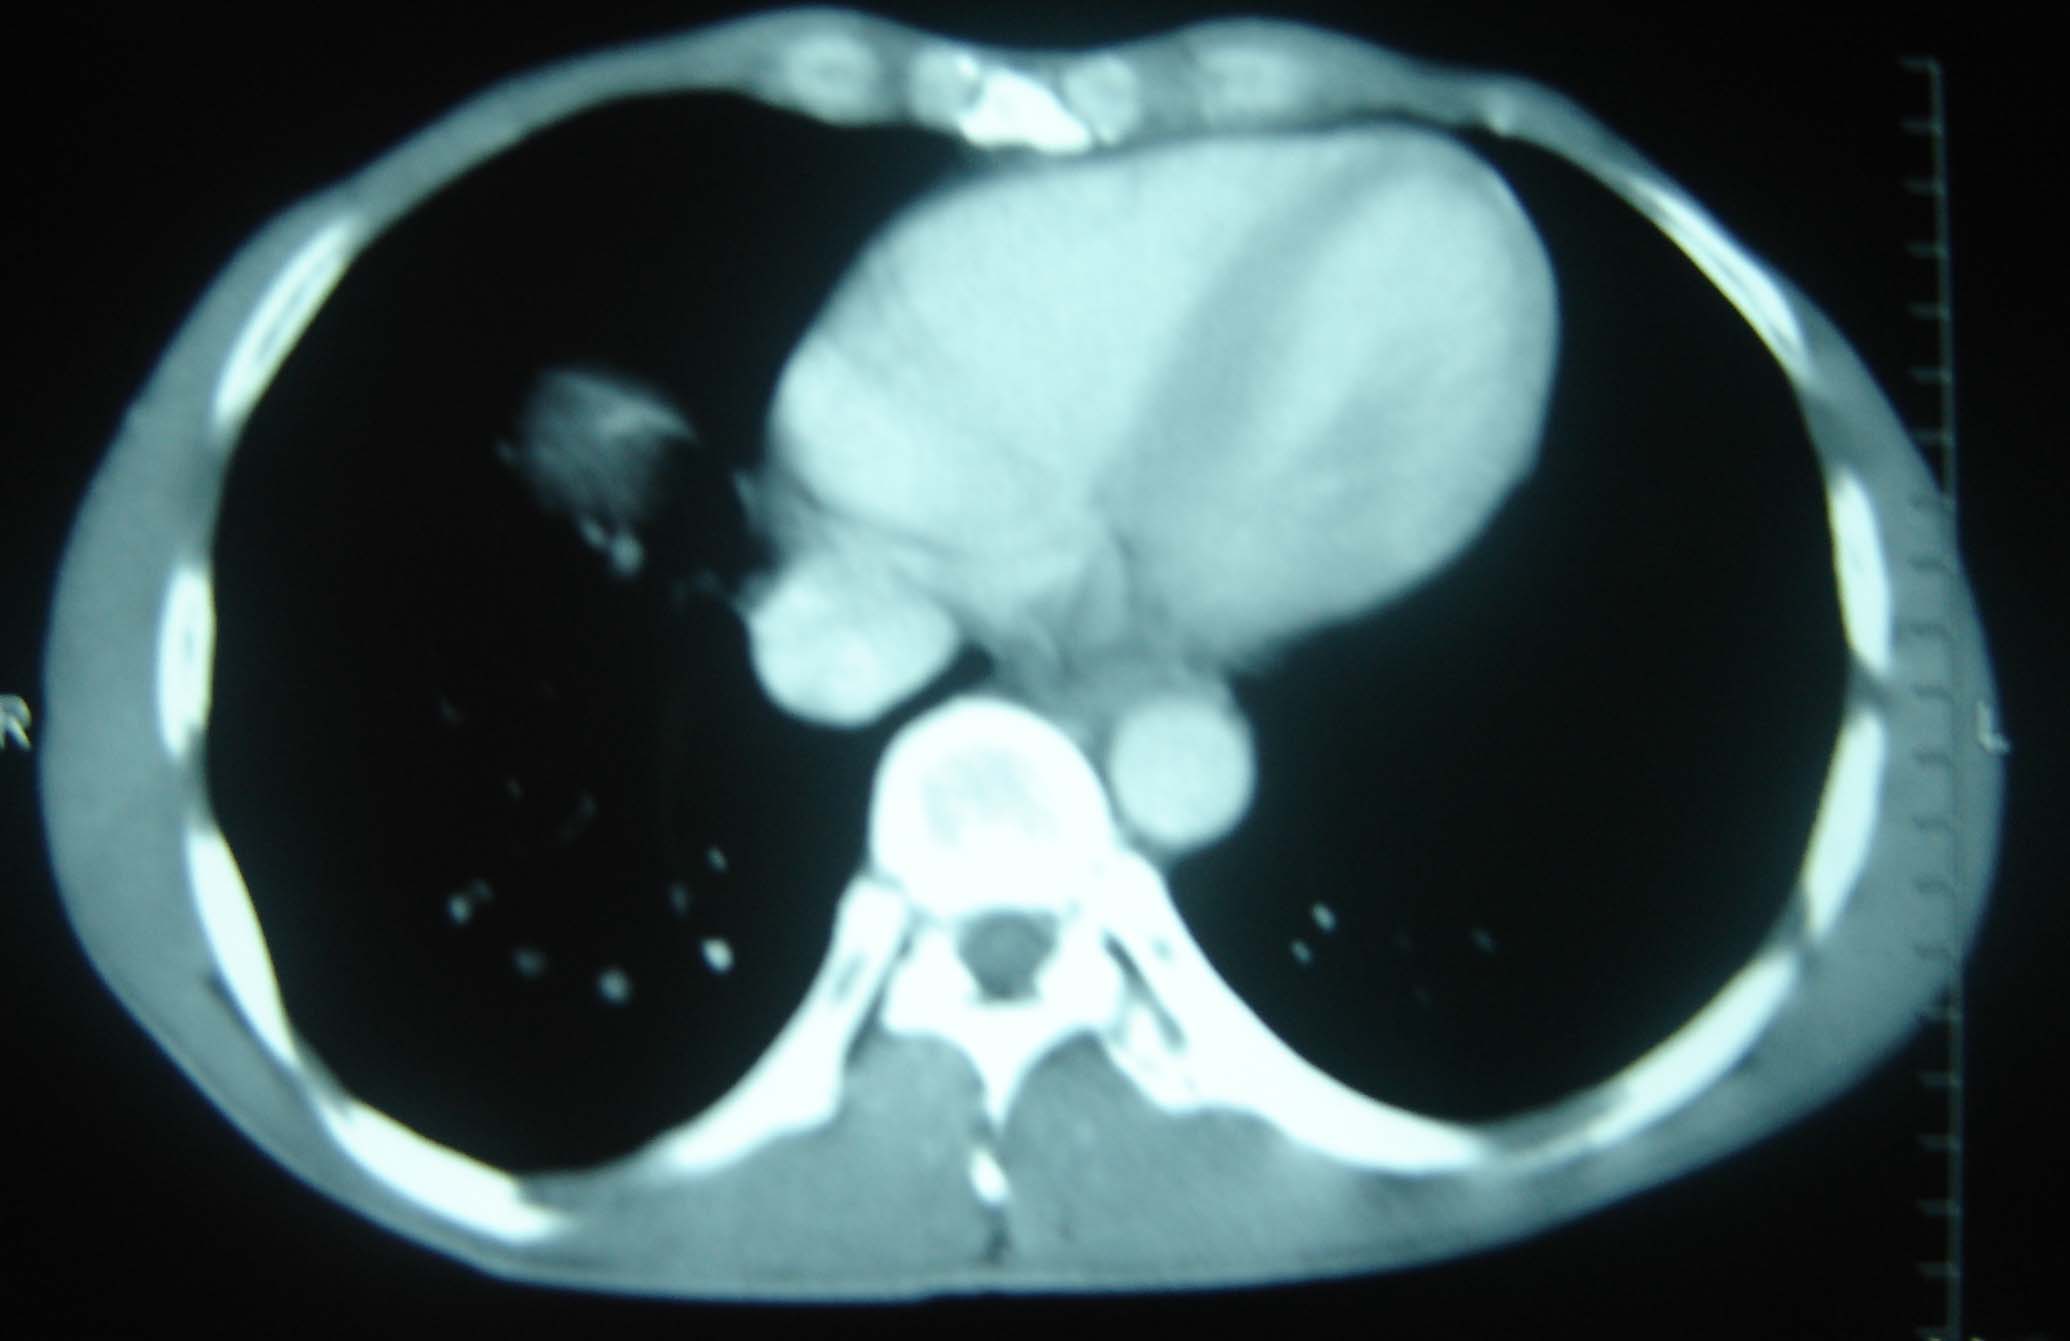

标题: CT25321:两肺多发结节 请会诊 [打印本页]

标题: CT25321:两肺多发结节 请会诊

男 、43岁,咳嗽胸痛,装修工,平时接触粉尘较多,有吸烟史10多年,纤维支气管镜检查未发现异常,胃镜、腹部b超检查亦未发现异常,颈部淋巴结活检未发现肿瘤细胞。

1)考虑双肺及胸膜多发性转移瘤。2)肺气肿。